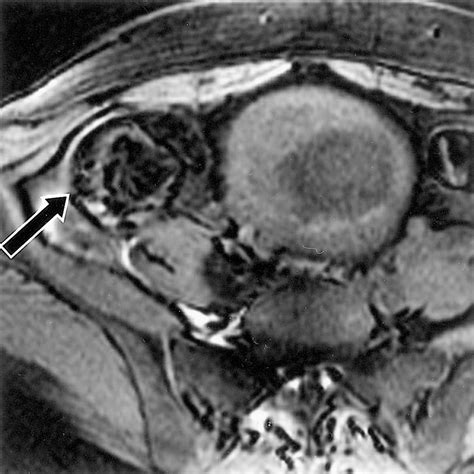

When doctors request scans, they are looking for specific visual identifiers. Imaging techniques such as CT scans, MRIs, and ultrasounds are standard. In these images, a teratoma often appears as a complex mass with both cystic (fluid-filled) and solid components. The presence of fat, calcifications (which look like bone or teeth on an X-ray), and soft tissue elements are hallmark signs that radiologists use to identify the growth.

While looking for Teratoma Cancer Pictures online, patients may see varying representations, but it is important to note that internal clinical imaging (like an MRI) looks significantly different from external surgical photography. Radiology provides the map for surgical intervention, helping surgeons understand the proximity of the tumor to vital organs.